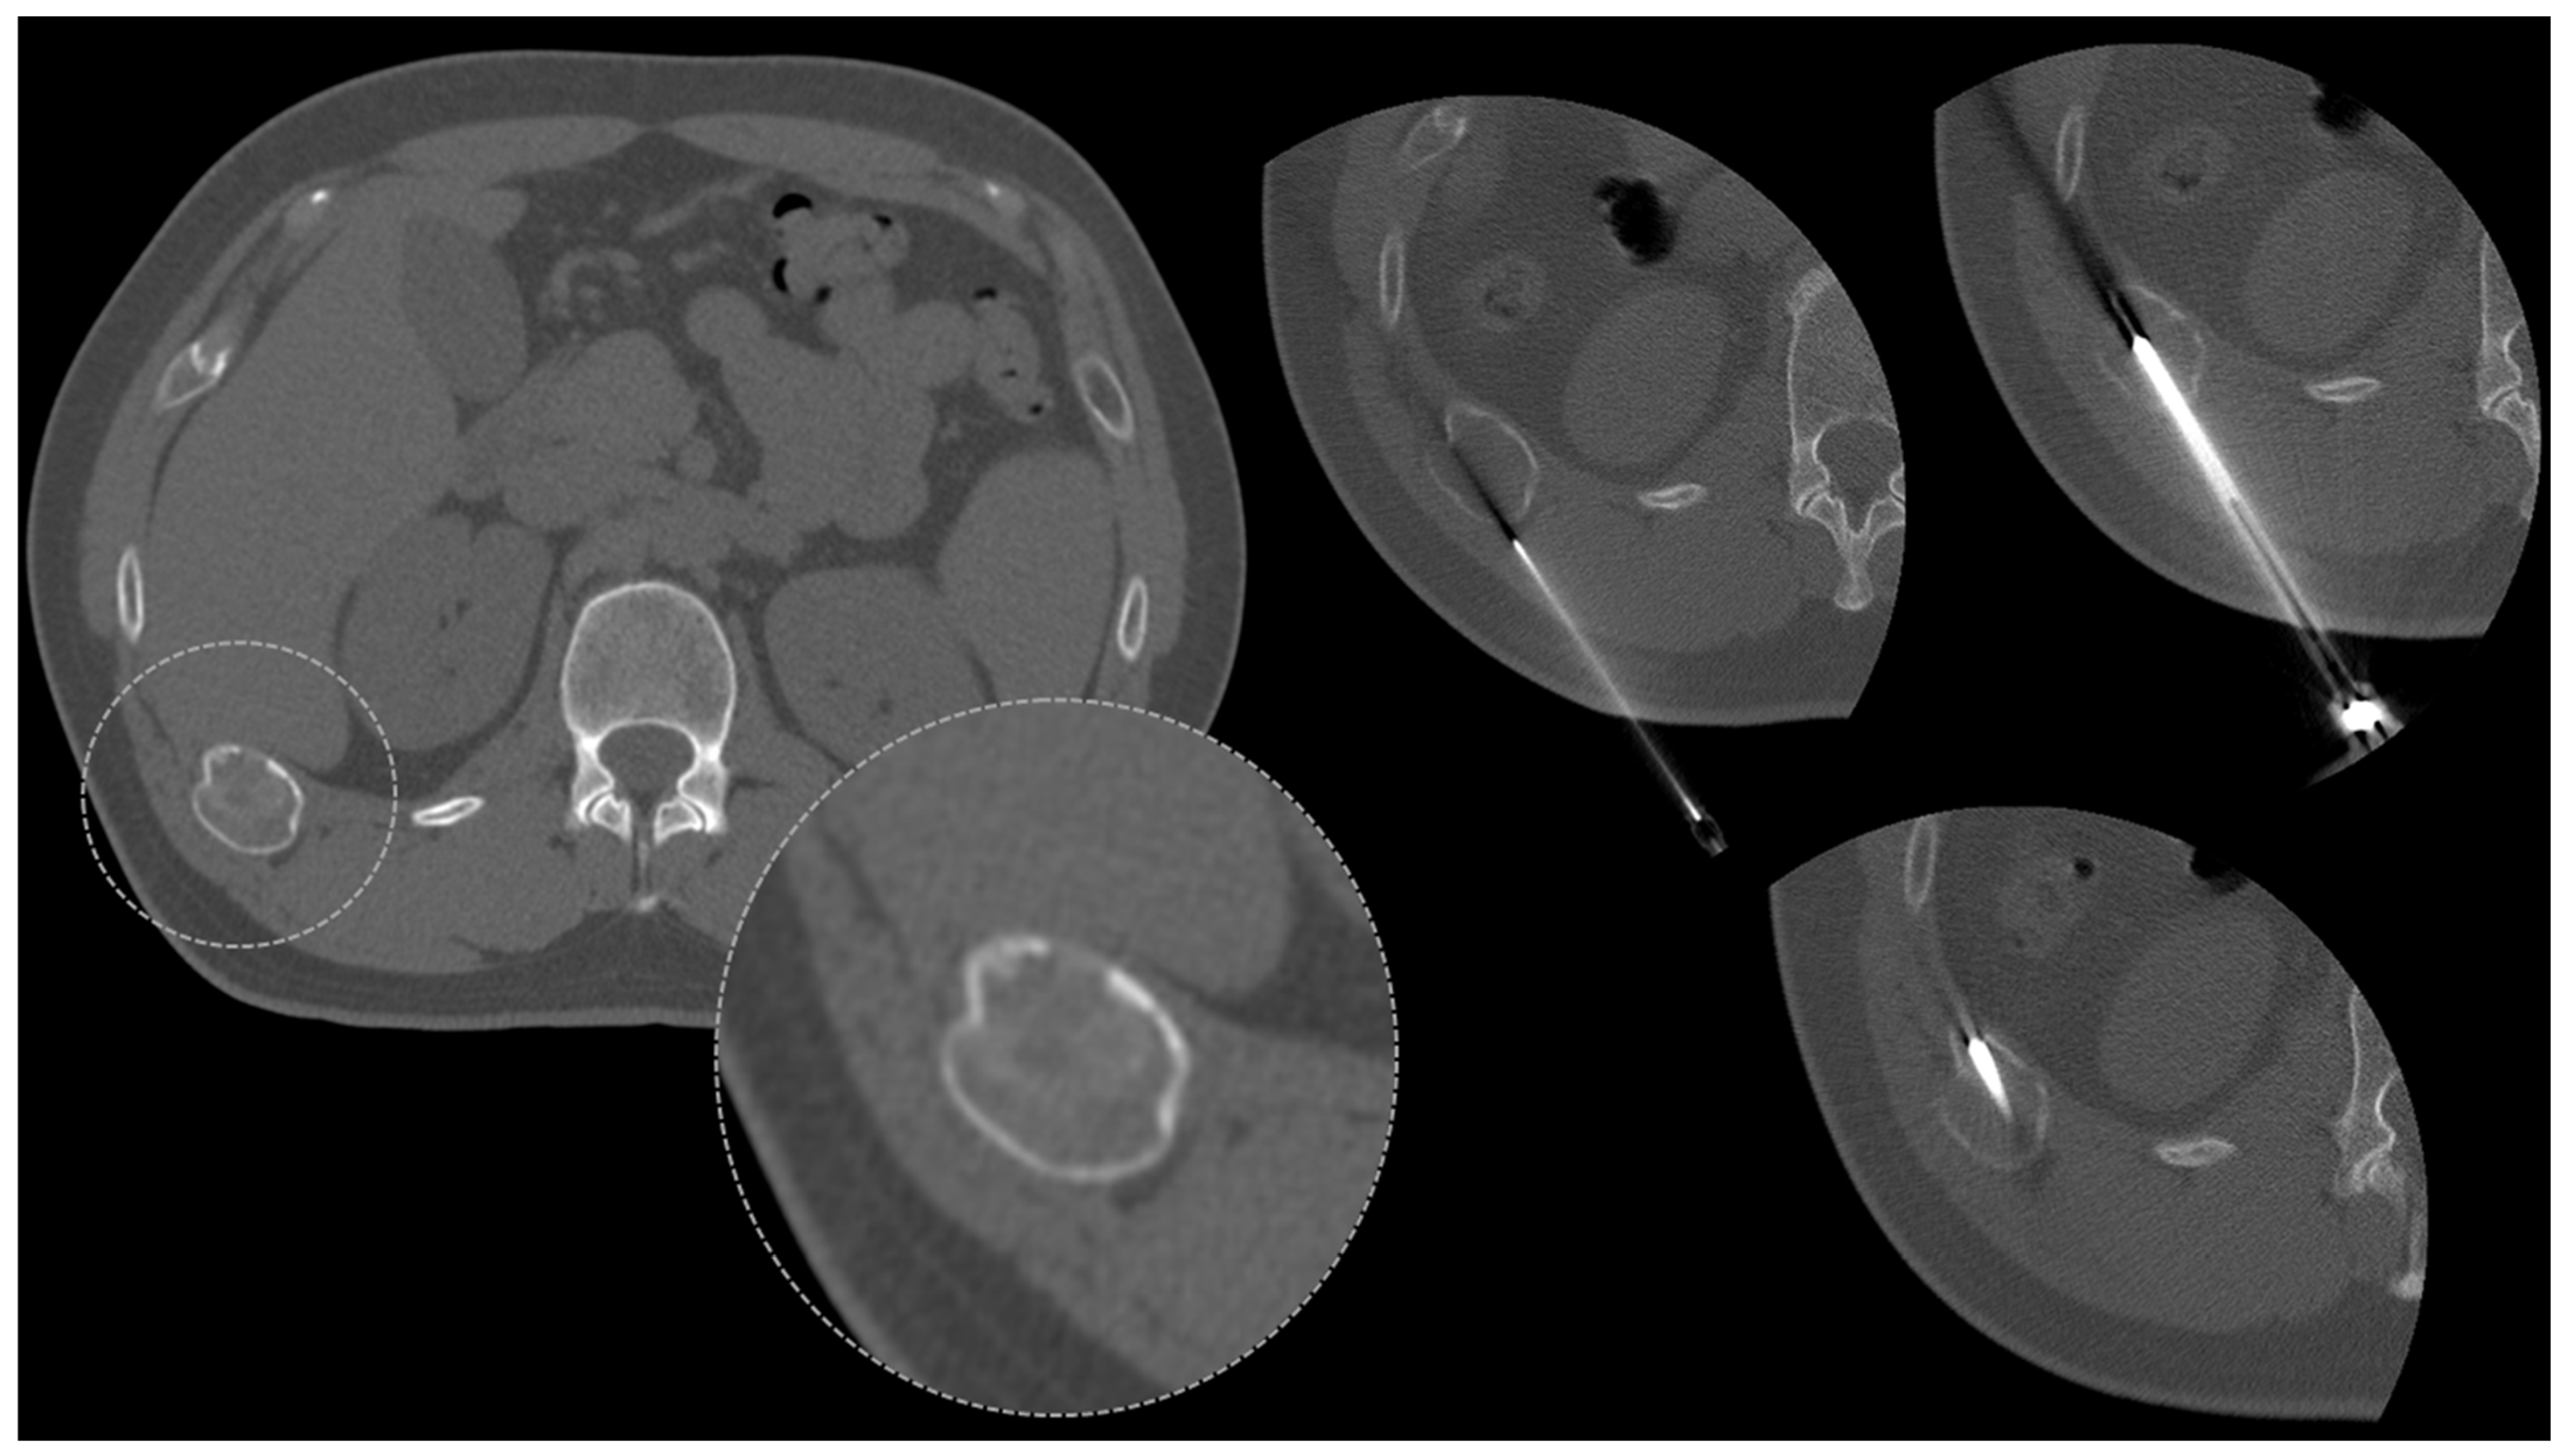

2.5. The Pelvis

- Donners, R.; Fotiadis, N.; Figueiredo, I.; Blackledge, M.; Westaby, D.; Guo, C.; de la Maza, M.d.l.D.F.; Koh, D.-M.; Tunariu, N. Optimising CT-guided biopsies of sclerotic bone lesions in cancer patients. Eur. Radiol. 2022, 32, 6820–6829. [Google Scholar] [CrossRef]